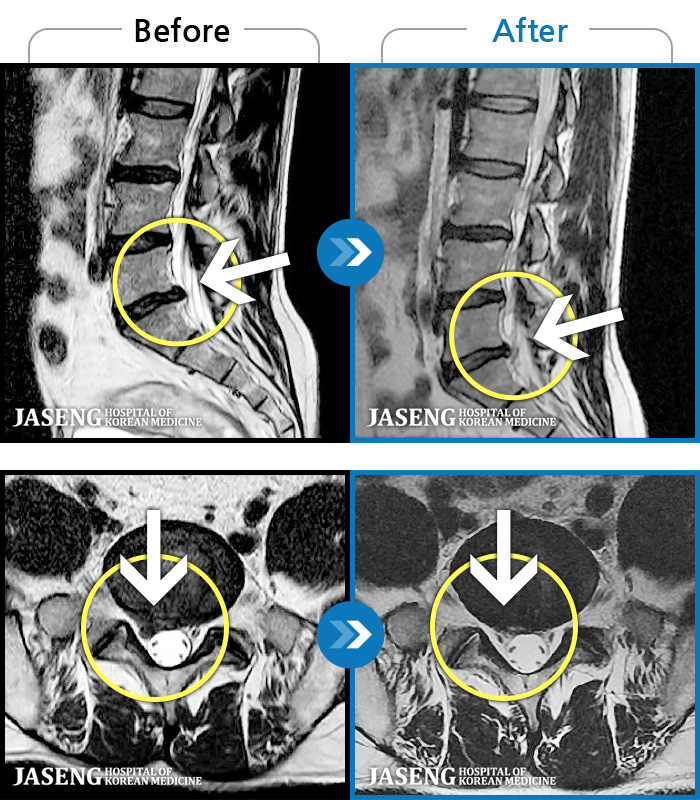

MRI ġ

1,299 MRI ũ ʸ Ȯϼ.